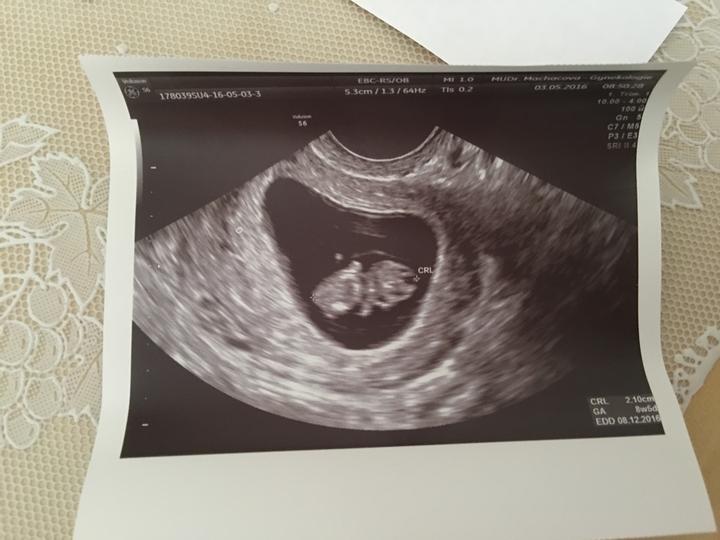

Tááááák!!! Dnešní kontrola naprosto v pořádku!! Moč v pořádku!! 💜 nám bije o stošest..vyrostli sme na 4,2cm a termín porodu se nám tím pádem posunul na 6.12.!! Dělala nám i takový předčasný prvotrimestrální screening (nosní kůska je a nuchální projasnění je v normě) takže sem o něco klidnější!! Mimčo si cucalo paleček a vesele se převalovalo ve vodičce 🙂 bude to asi plavec :D Další kontrola 15.6. a mezitím 2.6. prvotrimestrální screening 🙂 🙂 🙂 Sem nadšena 🙂